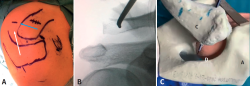

Figura 1. Preparación de túnel clavicular anteroposterior. El paciente en posición de silla de playa, hombro derecho. A: vista superior, se marcan prominencias óseas. La flecha azul muestra la dirección del túnel clavicular anteroposterior y la posición de la incisión cutánea para el paso de la broca percutánea acromioclavicular previamente determinada por radioscopia. La flecha blanca muestra la dirección del túnel acromial; B: vista anterior con fluoroscopia intraoperatoria del túnel clavicular anteroposterior; se puede identificar la broca canulada en el centro de la clavícula y a 1 cm de la línea articular; C: vista superior (modelo sintético), broca canulada de 2,4 mm a través de la clavícula de anterior a posterior. A: acromion; C: clavícula; D: broca canulada.